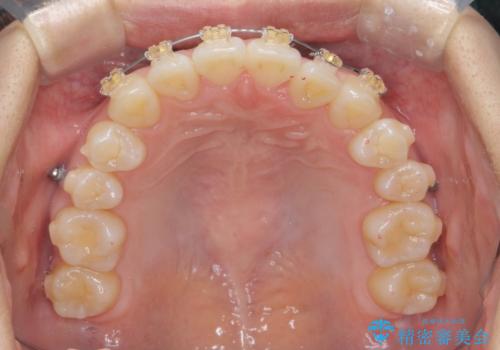

- インビザライン +部分ワイヤー矯正

マウスピース矯正システムインビザラインで歯の後方移動、咬合関係の修正を行ったのち、引っ込んでいる左上2をワイヤーを用いて短時間で引き出す治療計画としました。

部分ワイヤー矯正を行なったことで約3ヶ月という短期間で前歯を綺麗に並べることができました。